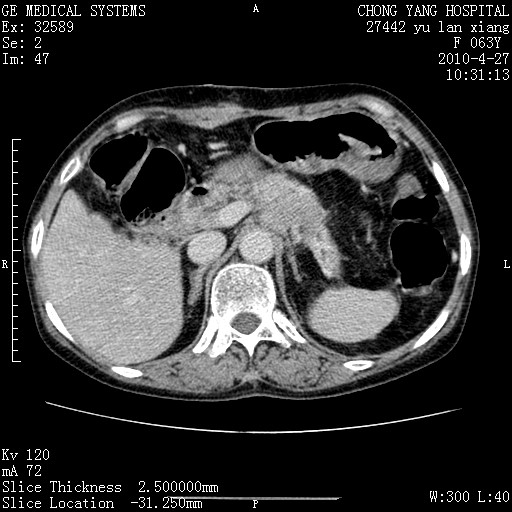

标题: CT26066:F63Y 上腹正中压痛半月,CA199:7400u/ml,MR示胰腺炎伴 [打印本页]

胰腺癌侵犯腹腔动脉干-分支、胃壁、左侧膈肌伴胰周及腹膜后淋巴结转移、胆囊切除术后。

胰腺癌侵犯腹腔动脉干-分支、胃壁、左侧膈肌伴胰周及腹膜后淋巴结转移、胆囊未显影。